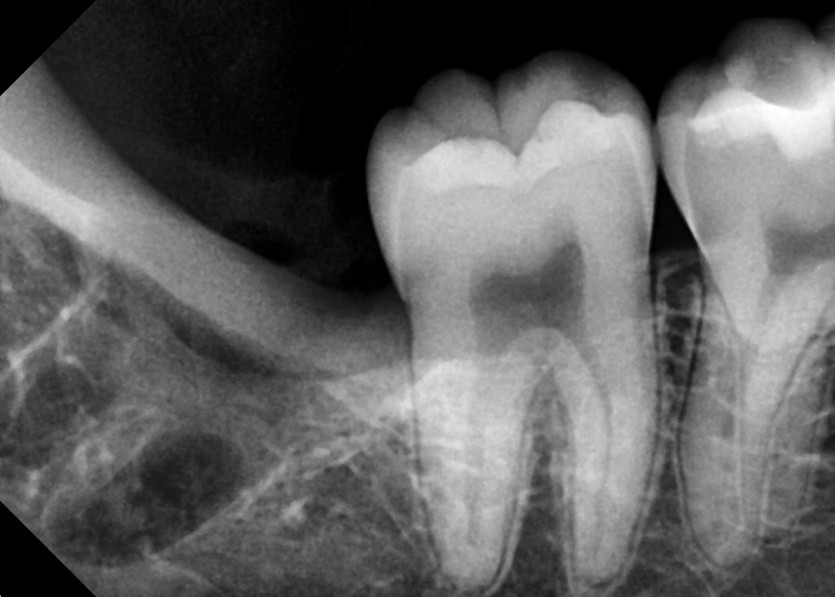

#48 사랑니 발치

구강 외과 전문의가 당일 발치했습니다.